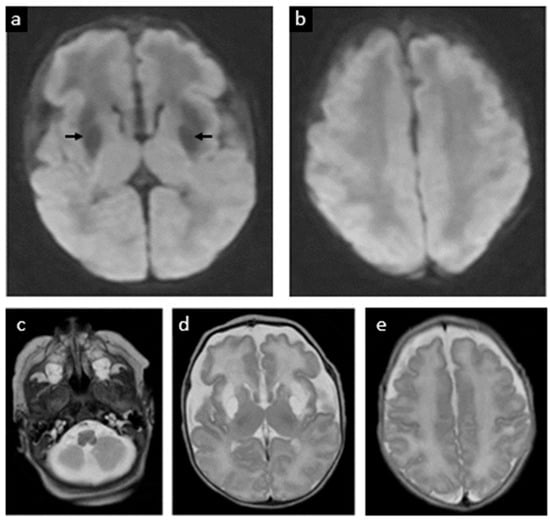

| 12 | Schwahn et al., 2024 (Patient A) [21] | No | None reported | Day 7 | Term | No seizure control. Severe dystonic and spastic quadriplegia. Received cPMP for 7 days before brain MRI results showed widespread severe diffusion restriction and signs of brain necrosis |

| 13 | Schwahn et al., 2024 (Patient B) [21] | No | None reported | Day 3 | Term | No seizure control. Severe dystonic and spastic quadriplegia. Received cPMP for 8 days before stopping due to lack of benefit |

| 14 | Schwahn et al., 2024 (Patient C) [21] | No | None reported | Day 4 | Term | No seizure control. Severe dystonic and spastic quadriplegia. Received cPMP for 22 days before stopping due to lack of benefit |